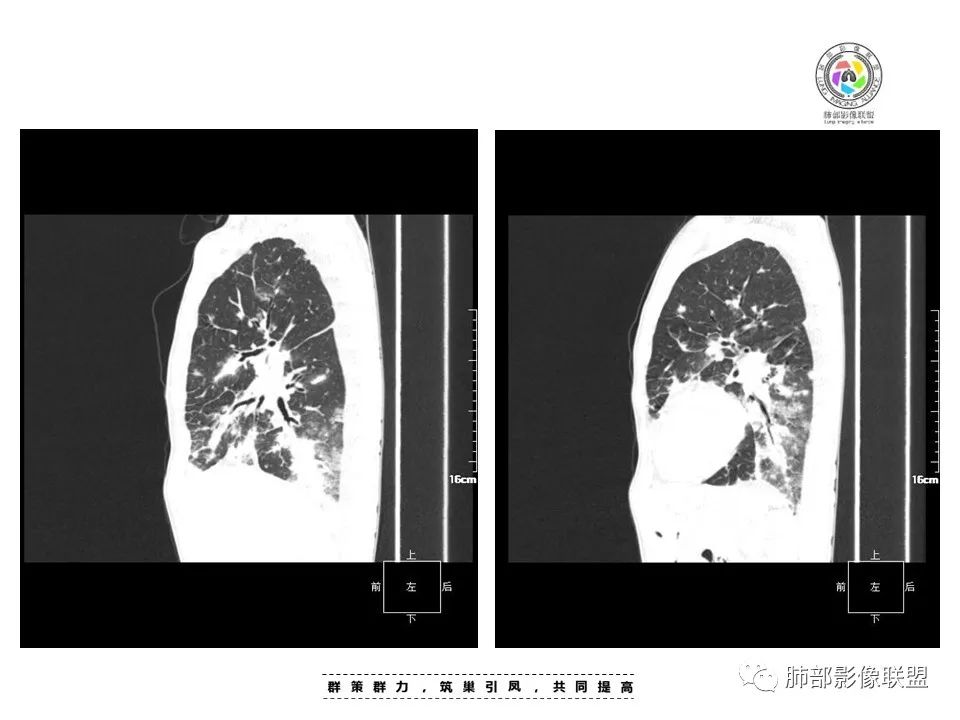

周一晚读病例:男性45岁,发热、纳差,全身散在暗紫色皮疹,结合CD4,符合HIV;肺部影像表现:两肺散在实性结节及磨玻璃密度影,实性结节伴晕征,部分沿支气管血管束分布,支气管血管束增粗,以两肺下叶为著,类似火焰征,双侧胸腔少量积液;首先考虑卡波西肉瘤,鉴别淋巴瘤增值性病变,淋巴瘤样肉芽肿/淋巴瘤,最后挂上马尔尼菲青霉菌病。

中年男性,发热、全身散在暗紫色丘疹,查CD4+T细胞64个/ul,临床信息提示AIDS并发卡波西肉瘤;CT提示双肺多发实性结节影及毛玻璃结节,部分呈点晕征,右上肺大姐姐边缘膨隆、分叶伴晕;双下肺结节沿支气管血管束分布,中轴间质增粗,部分支气管堵塞,叶间裂结节状增厚,部分结节胸膜下分布,可疑局部小叶间隔增厚,肺部病变呈淋巴分布特点,结合临床肺部病变考虑肺卡波西肉瘤,鉴别淋巴瘤。

两肺弥漫性性结节状、小片状及片状带晕的病灶,煎蛋征、点晕征,主要分布两肺中下叶,病灶周围小叶间隔增厚呈网格状影,部分病灶累及胸膜,伴两侧胸膜增厚。

2.本例双肺小叶间隔增厚明显,多发结节影及片状实性密度影,沿血管支气管束分布为主,两侧较为对称,病灶多环以磨玻璃晕,边界不清。

双侧胸腔少量积液。双肺门及纵隔未见明确肿大淋巴结,纵隔结构间隙模糊。

3.有学者将这种具有沿双肺支气管束分布的实性密度片影描述为“火焰征”,认为具有一定特征性,单就影像表现而言,这种影像表现也可以见于其他病损或多种病理改变的叠加。

1.结节型:两肺沿支气管血管束分布的结节影,呈火焰状或星芒状、挂果征,局部周围出血磨玻璃影(肺泡出血或水肿)。

2.支气管血管束增粗型:

肺门周围支气管壁呈“套袖样”改变。

3.肺炎渗出型:

斑片渗出影,部分融合呈“火焰样”,同时有火焰样结节,小叶间隔增厚等表现。

还可以有纵隔及腋下淋巴结增大,胸腔积液等表现。